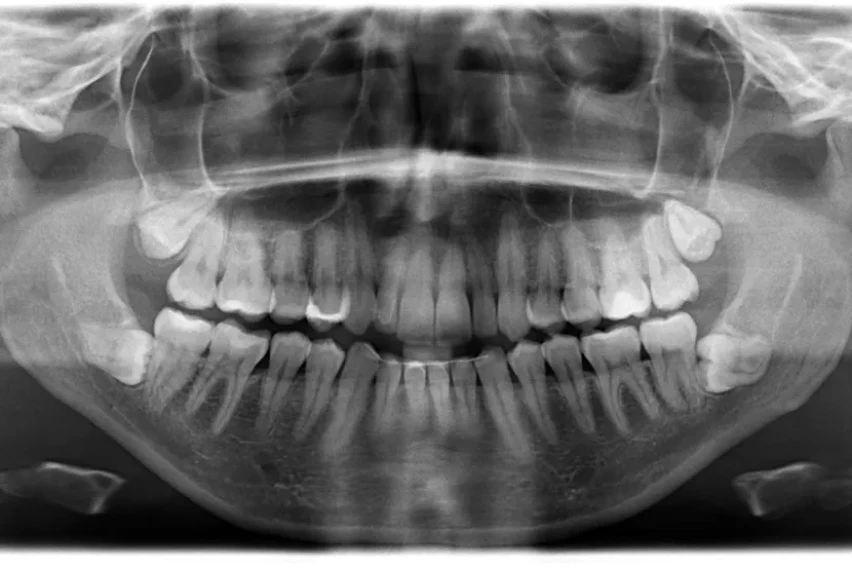

Меѓутоа подоцна рендгенската снимка на забите покажала дека постоеле уште четири заби што требало да изникнат.

„На почетокот од 2023 година сфатив дека имам вкупно 42 заби. За среќа повеќето заби пораснале право и без никакви компликации“, раскажал Мунианди.

„Луѓето вообичаено се многу изненадени и на почетокот им е тешко да поверуваат, особено кога ќе дознаат дека има 10 заби повеќе од една просечна личност, која обично има 32 заби“, додал Мунианди.

Исто така тој споделил дека стоматолозите кои ги прегледувале неговите заби за Гинисовата книга на рекорди (Guinness World Records) му соопштиле уште една изненадувачка вест – има уште два заби кои допрва треба да изникнат. Тој официјално ја добил титулата за најголем број заби кај мажи, додека женската верзија на рекордот ја држи Калпана Балан од Индија која има 38 заби.